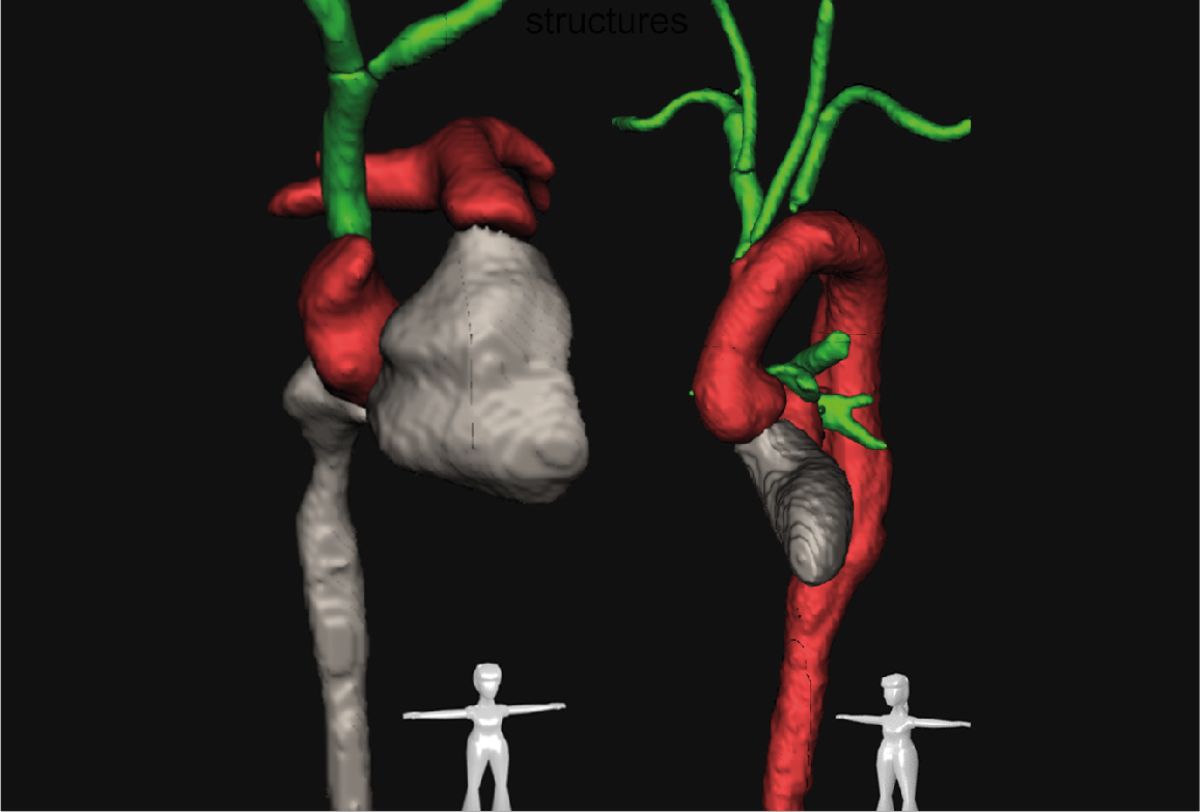

Mit menschlicher und künstlicher Intelligenz

Unsere Radiolog*innen prüfen und nutzen sie nun schon seit Jahren: die künstliche Intelligenz. KI-unterstützt erkennt und analysiert eine von unserern Wissenschaftlern entwickelte Software vollautomatisch anatomische Strukturen in Computertomografien, so etwa diesen Aortenbogen.